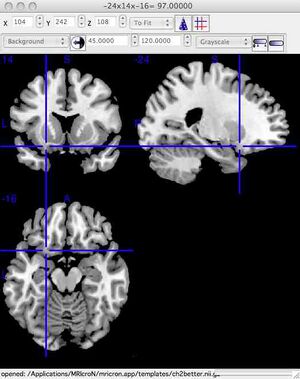

After successfully starting the program, you should see the following window. To make the images easier to see, you can enlarge the window. Go to Step 2, below. For Macintosh: The following instructions were tested with Mac OSX 10.8.2 running Safari. For different versions of OSX or other web browsers, the steps may be slightly different.

You should see the following window. To make the images easier to see, you can enlarge the window. To see only one plane enlarged, click View/Axial Only. For Linux (or if the above instructions don't work): please go to http://www.mccauslandcenter.sc.edu/mricro/mricron/install.html You are on your own for installation! REQUIRED Step 2: Explore the brain and learn structures found in labs 8 and 9Regardless of the platform (PC or Mac), the top left of the window shows a coronal view of the brain. The top right of the window shows a sagittal view of the brain. The bottom left of the window shows an axial (horizontal) view of the brain. Click the mouse at any brain location to move the blue viewing crosshairs. The dataset name is listed at the top of the MRIcroN window in Windows, at the bottom of the window for Mac. The correct brain to view is the "ch2" file (ch2.nii.gz). Load this file by selecting "File/Open/Templates/ch2.nii.gz". At the top of the program window are three boxes labelled "x", "y" and "z" that show the brain location. Enter each of the co-ordinates (x,y,z) listed below into MRIcron. This will take you to the structure whose name is on the first column. This material will make up part of the testing materials for these laboratories (lab exams). Name of structure / Coordinates of structure (enter into x,y,z boxes in MriCron)